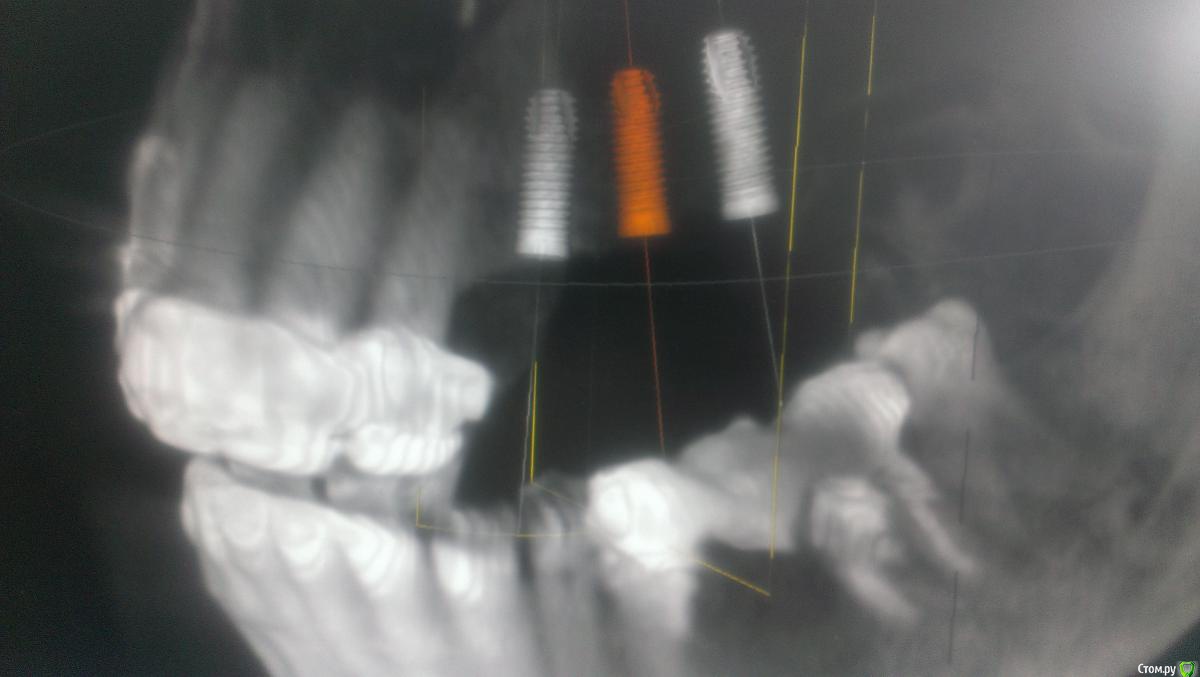

AlexFox Опубликовано 14 июля, 2016 Автор Поделиться Опубликовано 14 июля, 2016 Спасибо,коллеги.На основании ваших замечаний изменил постановку имплантов.Выложил фото,буду рад вашим коментариям Ссылка на комментарий

BugDan Опубликовано 14 июля, 2016 Поделиться Опубликовано 14 июля, 2016 (изменено) Я бы сделал синус с ауто-ксено 1:1 по причине чистой кортикалки в области моляров.Ставить ли импланты сразу или нет зависит от макродизайна имплантатов котрыми вы планируете пользоваться и опыта в первую очередь.На картинках планирования 23 стоит далековато от 22 , винт 5 стоит чуть медиальнее чем надо, а 6 сильно медиальнее чем нужно. Для страховки просмотрите латеральную стенку синуса на предмет артерии. Изменено 14 июля, 2016 пользователем BugDan Ссылка на комментарий

Astronaft Опубликовано 14 июля, 2016 Поделиться Опубликовано 14 июля, 2016 23 занчительно мезиальнее надо.Я бы ограничился 3 винтами задесь, поставив 25 под углом, что бы вышел на 26. 1 Ссылка на комментарий

Nazim_NV86 Опубликовано 14 июля, 2016 Поделиться Опубликовано 14 июля, 2016 Синус и имплантом "костенеет" быстрее чем без импланта. + удобнее и экономичнее. Дистальный я б не поставил сразу, ибо не стабилизируется. Первые два обязательно. Согласен с коллегами что трёх хватит. Самое сложное тут не синус, а верно расположить импланты. Ссылка на комментарий